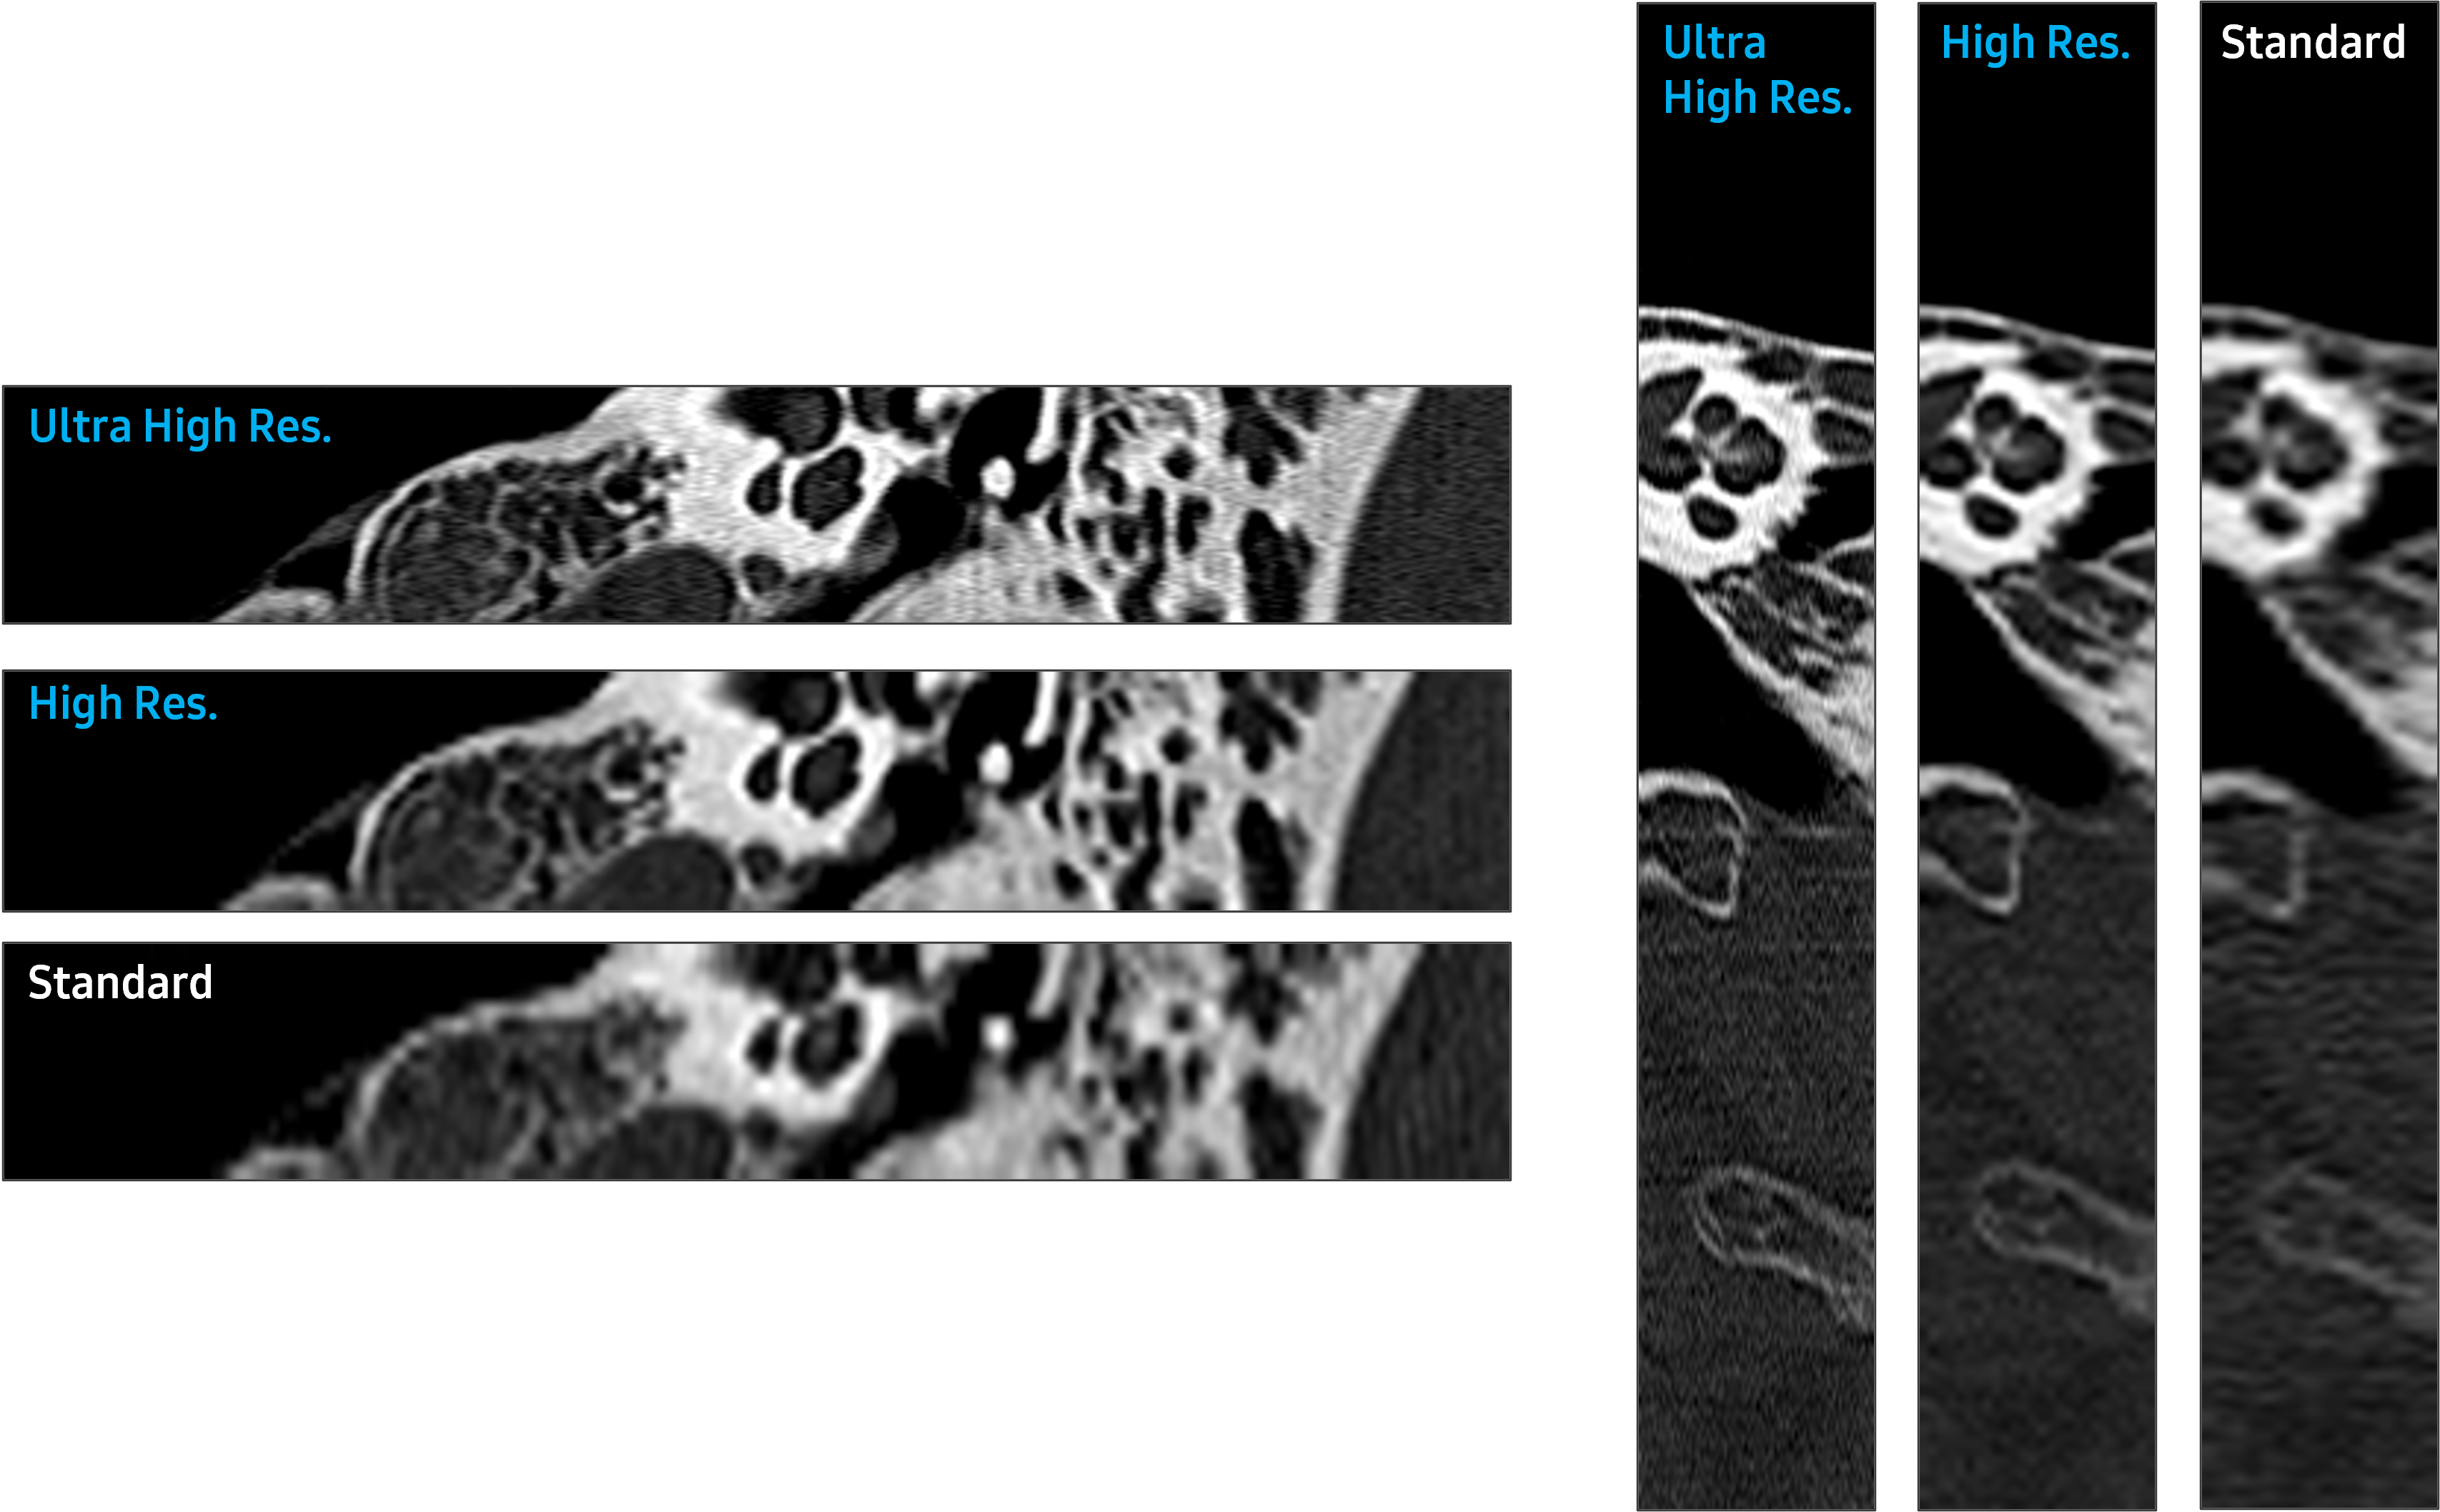

- Higher image resolution imaging for superior visualization of small structures

- Smaller detector size

Image Quality for Better Results

Photon Counting Detector (PCD) Technology

- Ultra High Resolution is under development, not available for commercial sale.